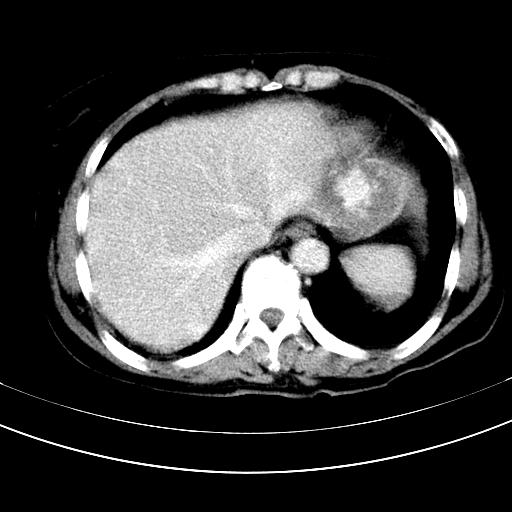

补充强化片

肝左叶及尾叶低密度灶,增强有渐进性明显强化,考虑血管瘤。胃内“充缺”首先要排除异物(食物),变换体位可鉴别。增强时机抓的不好,还应该有延时像。

谢谢楼主的增强片子,平扫没发现左侧肾上腺的问题很不好意思,可惜片子只有门脉期,所以还只有猜,肝脏的病灶在门脉期部分强化,首先考虑为血管瘤(其他的用一种病不好解释)胃要喝水就好了现在不好说是否有问题,左肾上腺的问题考虑是肿瘤。

做了增强后,可以明确胃是没有肿瘤的,肾上腺也没有肿瘤.肝左叶的病灶首先考虑血管瘤,应该再延迟,肝尾状叶的病灶仍不能排除肝癌的可能性.